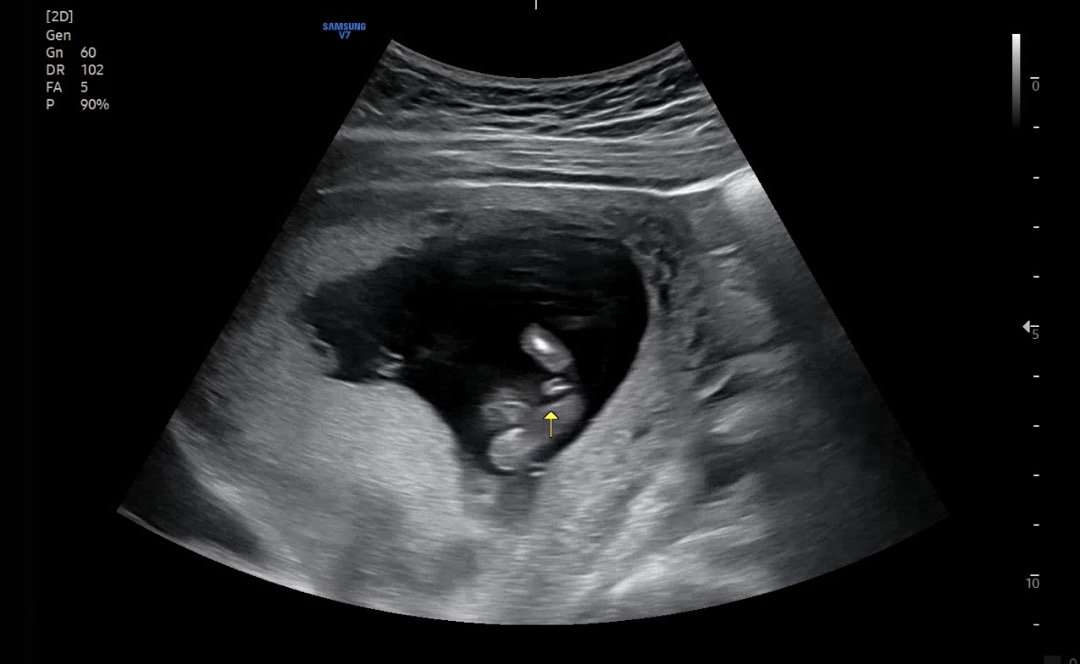

13주 3일 아들->딸 성별 반전 있을까요??😂😂

전 그래서 융모막 검사 기다려요 ㅎㅎ 쳇 gpt은 딸 같다고 하던데 ㅎㅎ 워낙 삼각형이 보여서 ㅠㅠ